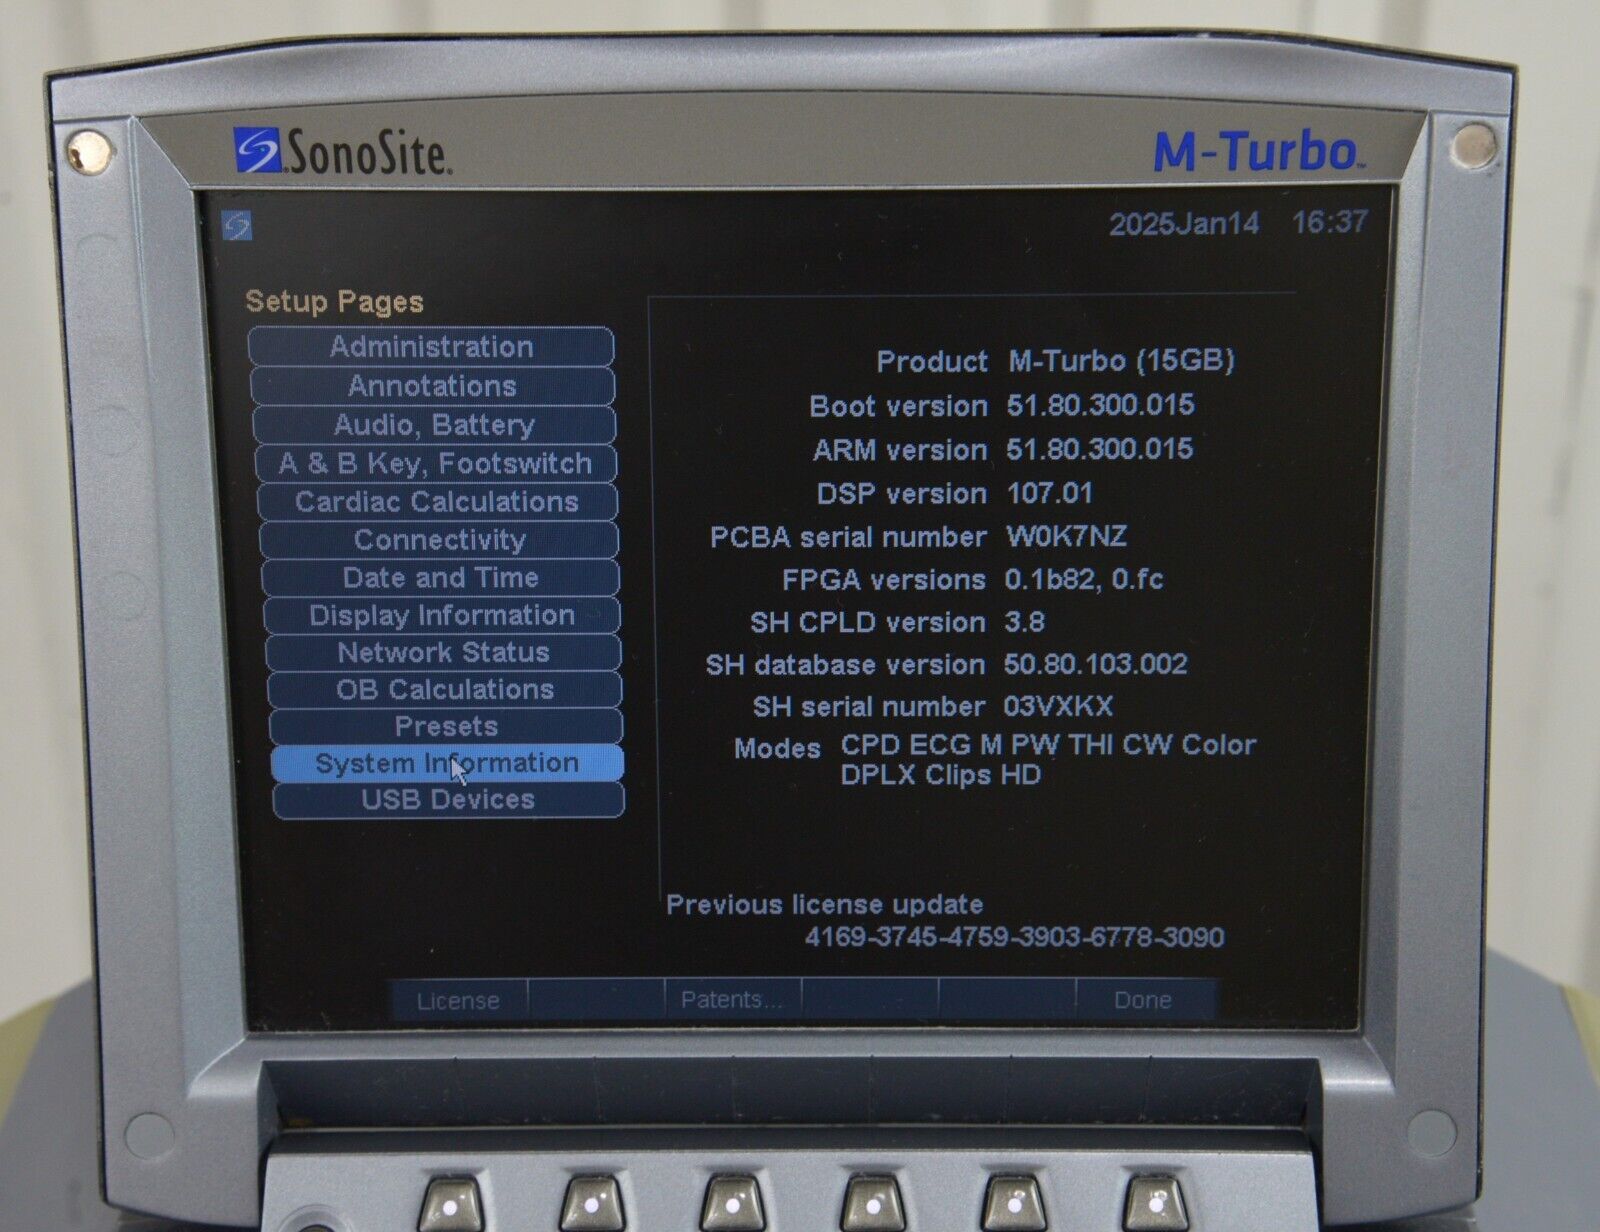

- Fujifilm Sonosite M-Turbo Ultrasound System W/ SonoSite P21x/5-1 MHz Transducer

January 15, 2025Fujifilm Sonosite M-Turbo Ultrasound System W/ SonoSite P21x/5-1 MHz Transducer

Fujifilm Sonosite M-Turbo Ultrasound System W/ SonoSite P21x/5-1 MHz Transducer

This Fujifilm Sonosite M-Turbo Ultrasound System W/ SonoSite P21x/5-1 MHz Transducer is in good working condition. This unit powers on properly and the display screen produces a clear picture. The buttons respond properly to selection and the connections are clean and in good condition. The battery holds a charge. There are a few minor scuff marks from previous use (see photos). This item comes with a 30 day satisfaction guarantee. Includes everything displayed in the photos and nothing else.